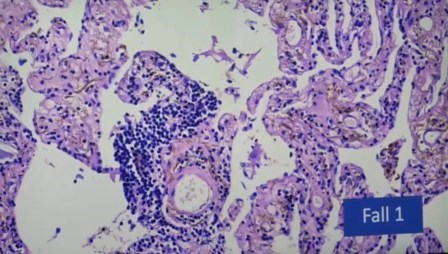

He aquí lo mostrado. Primero, en corazón:

Pulmón

Daño alveolar difuso, no es alveolitis. Sólo se ven los linfocitos por el colapso

Aglomeración de linfocitos alrededor de un vaso

Incluso se ven los folículos, no deberían estar allí porque solo deberían estar en una reacción alérgica y aquí no hay nada exógeno, es endógeno